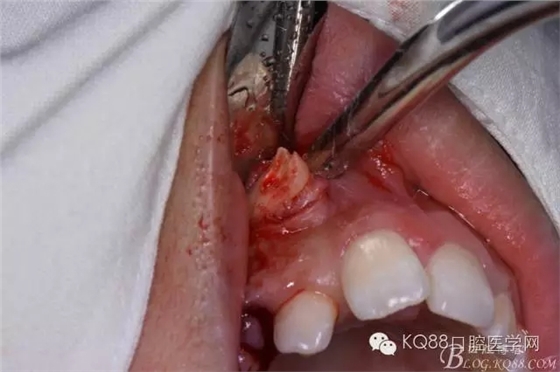

患者、女、高xx、17歲,主訴:外院轉(zhuǎn)診要求拔除埋伏牙。??茩z查:53殘根滯留、牙根斷面位于齦下,cbct檢查:13高位埋伏,牙冠壓迫12牙根的遠中面,牙根未見吸收,經(jīng)我院正畸科會診,建議拔除13、53,然后再正畸治療?;颊咄庵委煼桨福g前簽知情同意書。 拔牙過程: 圖1.術前的cbct檢查:13位于12遠中根尖區(qū),13牙根接近上頜竇、53牙根滯留。 圖2.口內(nèi)觀:53滯留、牙根斷面位于齦下,12牙冠唇傾。 圖3.合面觀:12畸形舌側(cè)窩、腭側(cè)沒有明顯隆起 圖4.首先拔除53,然后在23唇側(cè)區(qū)域的前庭溝處的黏膜做弧形切口 圖5. 翻瓣 圖6.去骨 圖7.暴露出13牙冠 圖8.高速渦輪機分牙、目的是盡量少去骨。 圖9. 從頸部截分13 圖10. 13牙冠頸部分牙情況 圖11.再把牙冠分成近中、遠中兩部分。 圖12.取出13牙冠 圖14.取出13牙根 圖15.取出的13的牙根 圖16.拔除13牙后形成的拔牙創(chuàng)。 圖17.拔除的13. 圖18.縫合